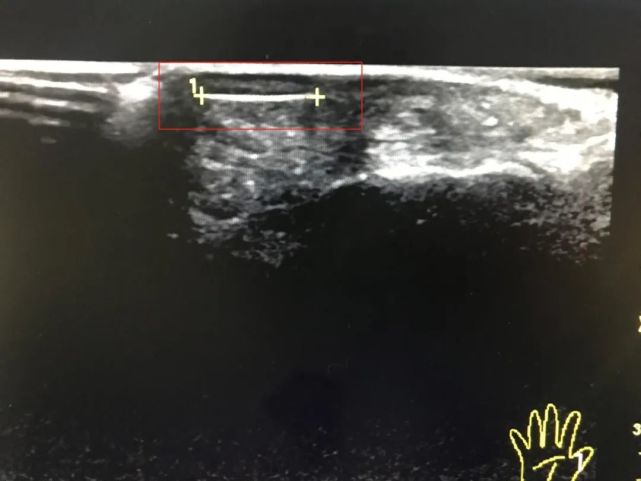

超声检查发现:余大伯拇指皮下距皮肤0.15cm处可见0.9cm长的“头发丝”样强回声,考虑异物,并伴有软组织肿胀。

余大伯有点急了,强烈要求取出异物。但由于刺又细又短,临床定位困难。为了能尽快解除余大伯痛苦,骨科宋泽辉医师和B超梁妃医师商量后决定,尝试 结合超声定位来取刺治疗。

因为很细,是个玻璃丝,所以取的时候比较困难,怕跑又怕弄断。经过超声的反复引导、定位及医生的反复探查下,经过1个多小时的努力,终于成功将异物取出,折磨多日的疼痛立马有所缓解。